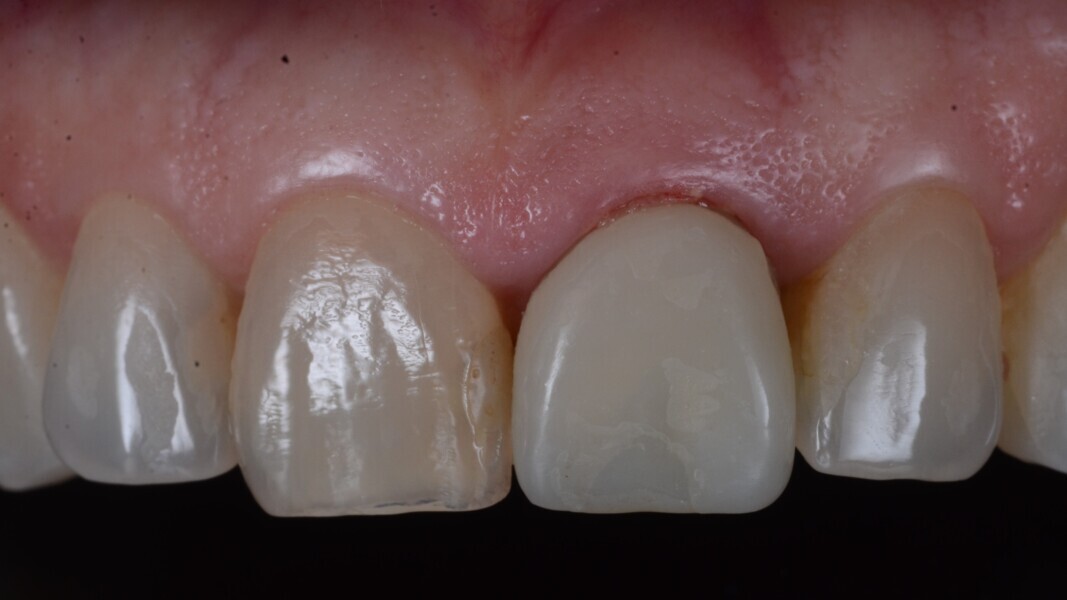

Fig. 12: Final implant position assessment in relation to gingival margins.

Fig. 11: Final implant position assessment.